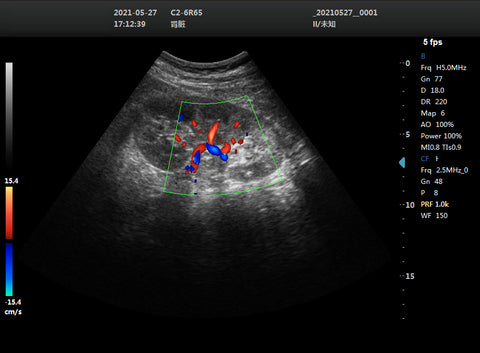

• Convex transducers: These have a curved arrangement of piezoelectric crystals that produce a convex beam of sound waves. They are used for imaging deeper structures, such as abdominal organs, fetal development, and pelvic organs. They have a low frequency and a good resolution in the far field, but a poor resolution in the near field.